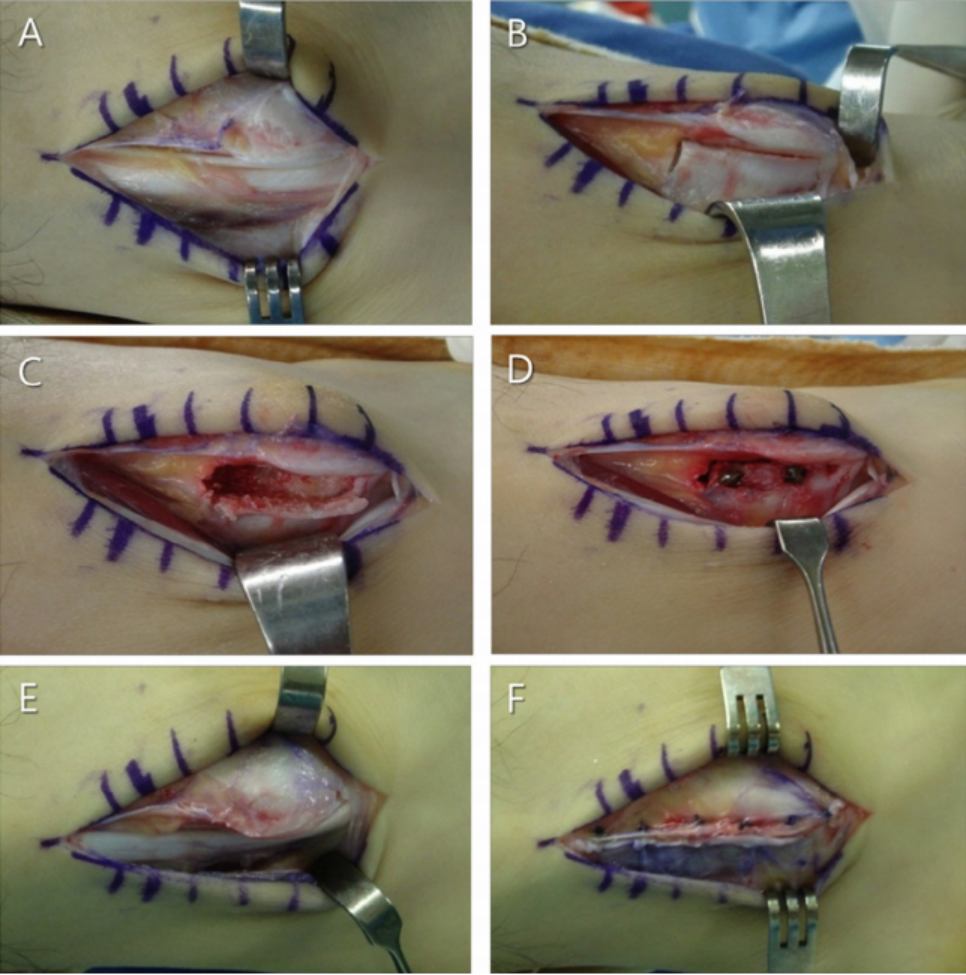

如不合并其他病理改变,可将支持带和骨膜直接缝合于外踝骨质上。

SPR撕脱开放手术锚钉修复

SPR撕脱关节镜手术锚钉修复

使用跟腱、跖肌腱、腓骨短肌腱等肌腱的一部分加强固定腓骨支持带。

通过切除腓骨后方部分骨质,可以加深腓骨沟,改变、并增加了腓骨肌腱的稳定。

大部分急性损伤可以使用直接缝合修复,对慢性损伤则需根据患者的具体病理改变选择,如单纯的支持带结构损伤,可以直接缝合修复。如果直接修复不够稳定,需用其他组织加强。如果腓骨外踝窝较浅时,就需要使用加深手术。